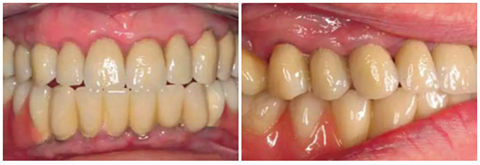

有一位病人因為口腔鱗狀細胞癌而進行了部分舌和口底的切除術(shù),并進行了輔助放療。盡管由于組織的纖維化,外科準(zhǔn)備及創(chuàng)口縫合時變的非常困難,但患者的種植手術(shù)最終仍然成功了?;颊吲宕髁肆甑牧x齒,并且一直沒有出現(xiàn)問題。這部分的臨床過程及義齒情況詳見于圖8-18.

圖17& 18:Katharina Dietz-Epple醫(yī)生(Aalen, Germany)完成的冠修復(fù)(上頜)及可摘局部義齒修復(fù)(下頜)。